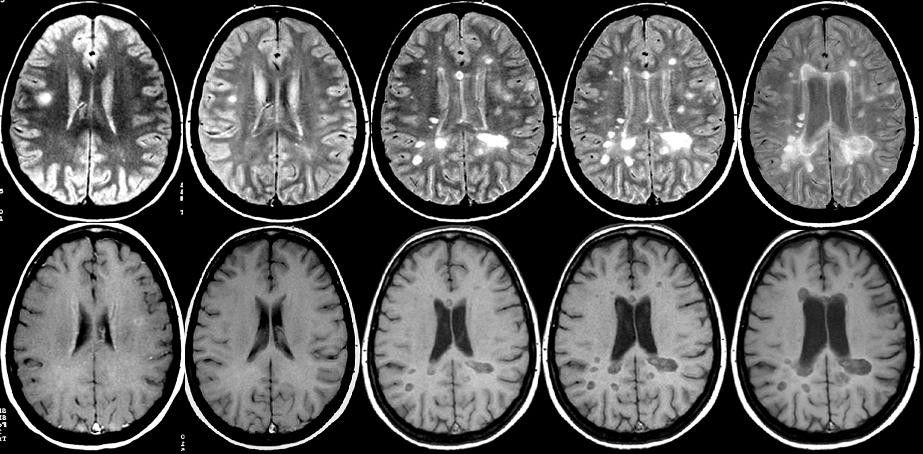

Serial axial T2-weighted (top row) and postcontrast T1-weighted (bottom row) spin-echo MRI images of brain performed at baseline, month 1, and month 2, in a patient with relapsing-remitting MS. Multiple hyperintense lesions, which suggest multifocal white-matter pathology, are visible on T2-weighted image at baseline. On postcontrast T1-weighted examination, some of these lesions are contrast-enhanced, which indicates local disruption of blood–brain barrier. New contrast-enhancing lesions can be observed at month 1 and month 2, which indicate dissemination of disease.

Image courtesy of Massimo Filippi